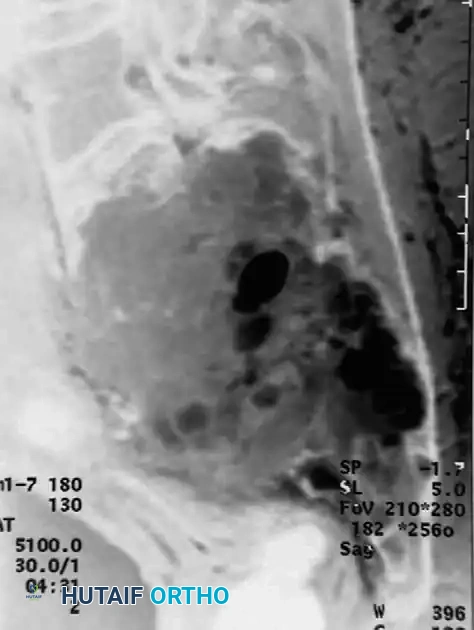

Advanced Imaging (MRI and CT)

Magnetic Resonance Imaging (MRI) is essential for evaluating the extent of the lesion, assessing articular cartilage integrity, and identifying secondary aneurysmal bone cysts (ABCs), which are present in up to 20% of patients. MRI typically reveals extensive bone marrow edema surrounding the lesion, which can be disproportionate to the tumor's size, further explaining the severe joint pain.

Computed Tomography (CT) is highly sensitive for detecting subtle intralesional calcifications and delineating the exact three-dimensional anatomy of the cortical margins, which is critical for planning the surgical approach and cortical window.